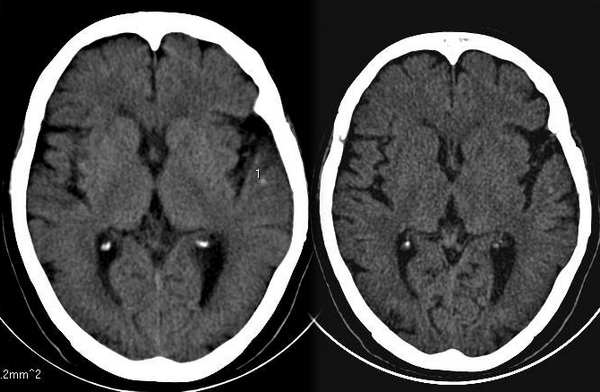

女,76岁,高血压病史二十余年。8小时前出现头晕,呕吐。无神经系统体征

体积小而密度高、边界较锐利,考虑钙化点,必要时复查。

1、左颞叶皮层点状钙化灶,患者年龄较大,多考虑生理性钙化。

2、脑沟裂增宽加深,脑萎缩。

左侧裂池旁小点状钙化,很难说是什么,只能说是血管钙化,血管畸形钙化亦不排除。脑皮质萎缩。